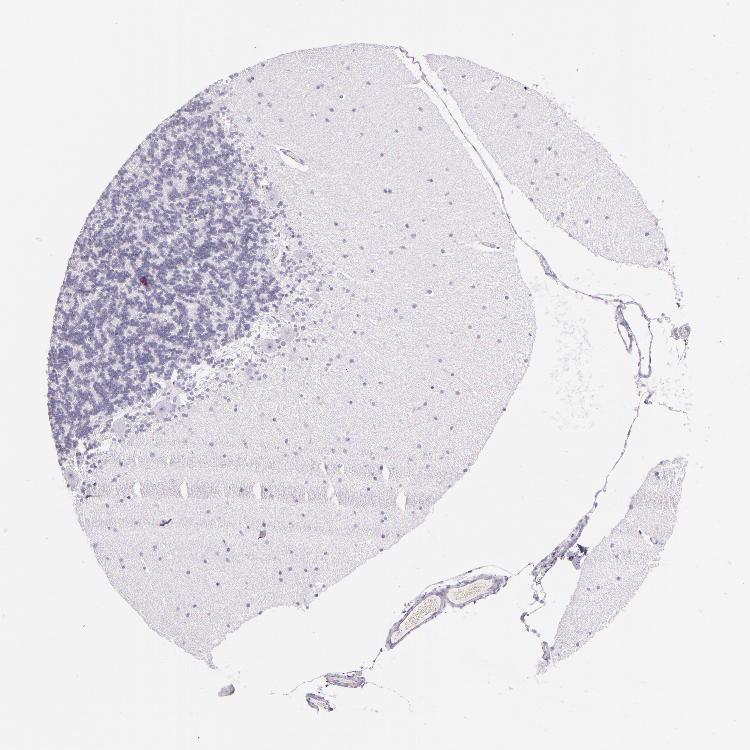

BRAIN CEREBELLUM Show tissue menu

CEREBELLUM - Expression summary

CEREBELLUM - Antibody stainingi

Antibody staining in the annotated cell types in the current human tissue is reported as not detected, low, medium, or high, based on conventional immunohistochemistry profiling in selected tissues. This score is based on the combination of the staining intensity and fraction of stained cells.

Each image is clickable and will lead to virtual microscopy that enables deeper exploration of all samples and also displays staining intensity scores, fraction scores and subcellular localization as well as patient and tissue information for each sample.

Antibody HPA002655Antibody HPA005990Antibody CAB002145

Purkinje cells MediumHighNot detected

Cells in granular layer LowNot detectedNot detected

Cells in molecular layer MediumLowNot detected